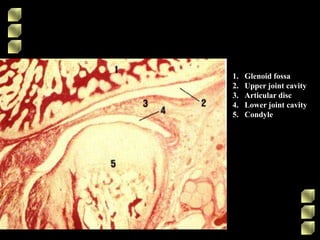

1. Glenoid fossa

2. Upper joint cavity

3. Articular disc

4. Lower joint cavity

5. Condyle

1. Glenoid fossa 2.Upper joint cavity 3. Articular disc 4. Lower joint cavity 5. Condyle